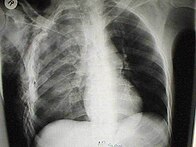

Significant cases of subcutaneous emphysema are easy to diagnose because of the characteristic signs of the condition.[1] In some cases, the signs are subtle, making diagnosis more difficult.[13] Medical imaging is used to diagnose the condition or confirm a diagnosis made using clinical signs. On a chest radiograph, subcutaneous emphysema may be seen as radiolucent striations in the pattern expected from the pectoralis major muscle group. Air in the subcutaneous tissues may interfere with radiography of the chest, potentially obscuring serious conditions such as pneumothorax.[18] It can also reduce the effectiveness of chest ultrasound.[27] On the other hand, since subcutaneous emphysema may become apparent in chest X-rays before a pneumothorax does, its presence may be used to infer that of the latter injury.[13] Subcutaneous emphysema can also be seen in CT scans, with the air pockets appearing as dark areas. CT scanning is so sensitive that it commonly makes it possible to find the exact spot from which air is entering the soft tissues.[13] In 1994, M.T. Macklin and C.C. Macklin published further insights into the pathophysiology of spontaneous Macklin's Syndrome occurring from a severe asthmatic attack.